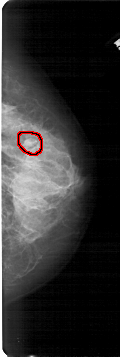

RIGHT_MLO LINES 5491 PIXELS_PER_LINE 2236 BITS_PER_PIXEL 12 RESOLUTION 43.5 OVERLAY

FILE: A_1682_1.RIGHT_MLO.OVERLAY

TOTAL_ABNORMALITIES 1

ABNORMALITY 1

LESION_TYPE MASS SHAPE OVAL MARGINS OBSCURED

ASSESSMENT 4

SUBTLETY 3

PATHOLOGY BENIGN

TOTAL_OUTLINES 1

BOUNDARY